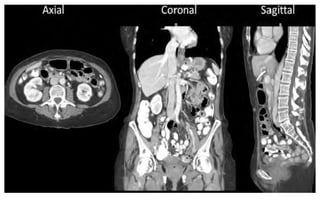

Modes of Acquisitions

Scout ,Surview , Topogram, Scanogram

Axial , Sequential Scanning

Spiral , Helical Scanning

Images reconstructed with different FOVs.

A, Reconstructed with 50-cm FOV.

B, Reconstructed with 50-cm FOV and interpolated to 10-cm FOV.

C, Targeted reconstruction to 10-cm FOV.

Field of view & The spatial resolution